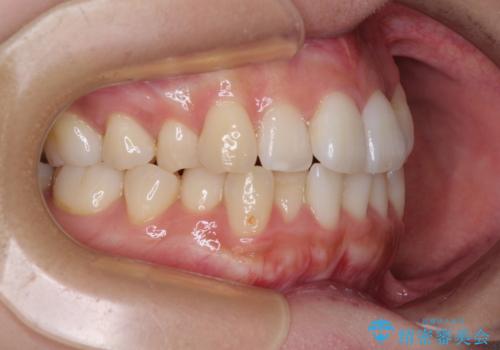

上顎歯列が下顎の歯列に対して狭小であり、一部下顎の奥歯が上顎よりも外側に位置している状態でした。

上顎の急速拡大装置を使用して上顎骨を側方に拡大することで上顎歯列を拡大し、下顎歯列も拡大できるようにすることで、歯列を整えることとしました。

上顎の拡大は、左右どちらに拡大していくのか予想が困難ですが、こちらの患者様では結果として上下正中が一致する方向に拡大され、非常にきれいな仕上がりとなりました。